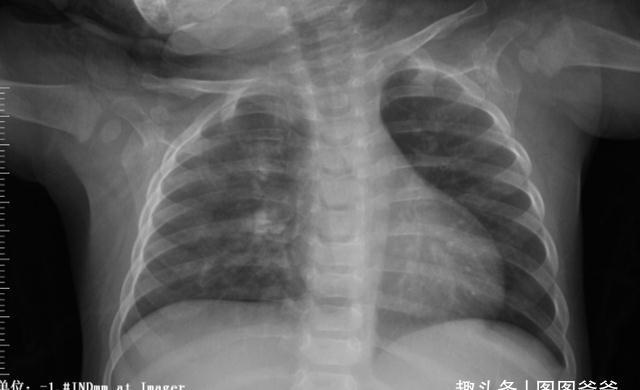

2、呼吸系统

孩子的积食问题和脾胃是密不可分的,当积食影响到肠胃以后,也会牵连到孩子的肺,也就是说如果孩子存在积食的问题,可能还会伴随着气管炎、咽炎、哮喘等呼吸疾病,对孩子的影响还是很大的。